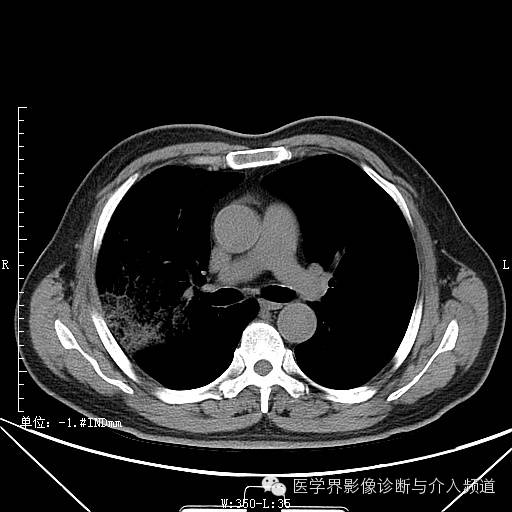

首次复查

首次复查:右肺实变范围加大,并可见磨玻璃与粟粒样结节影并存,同左肺亦出现磨玻璃及实变。